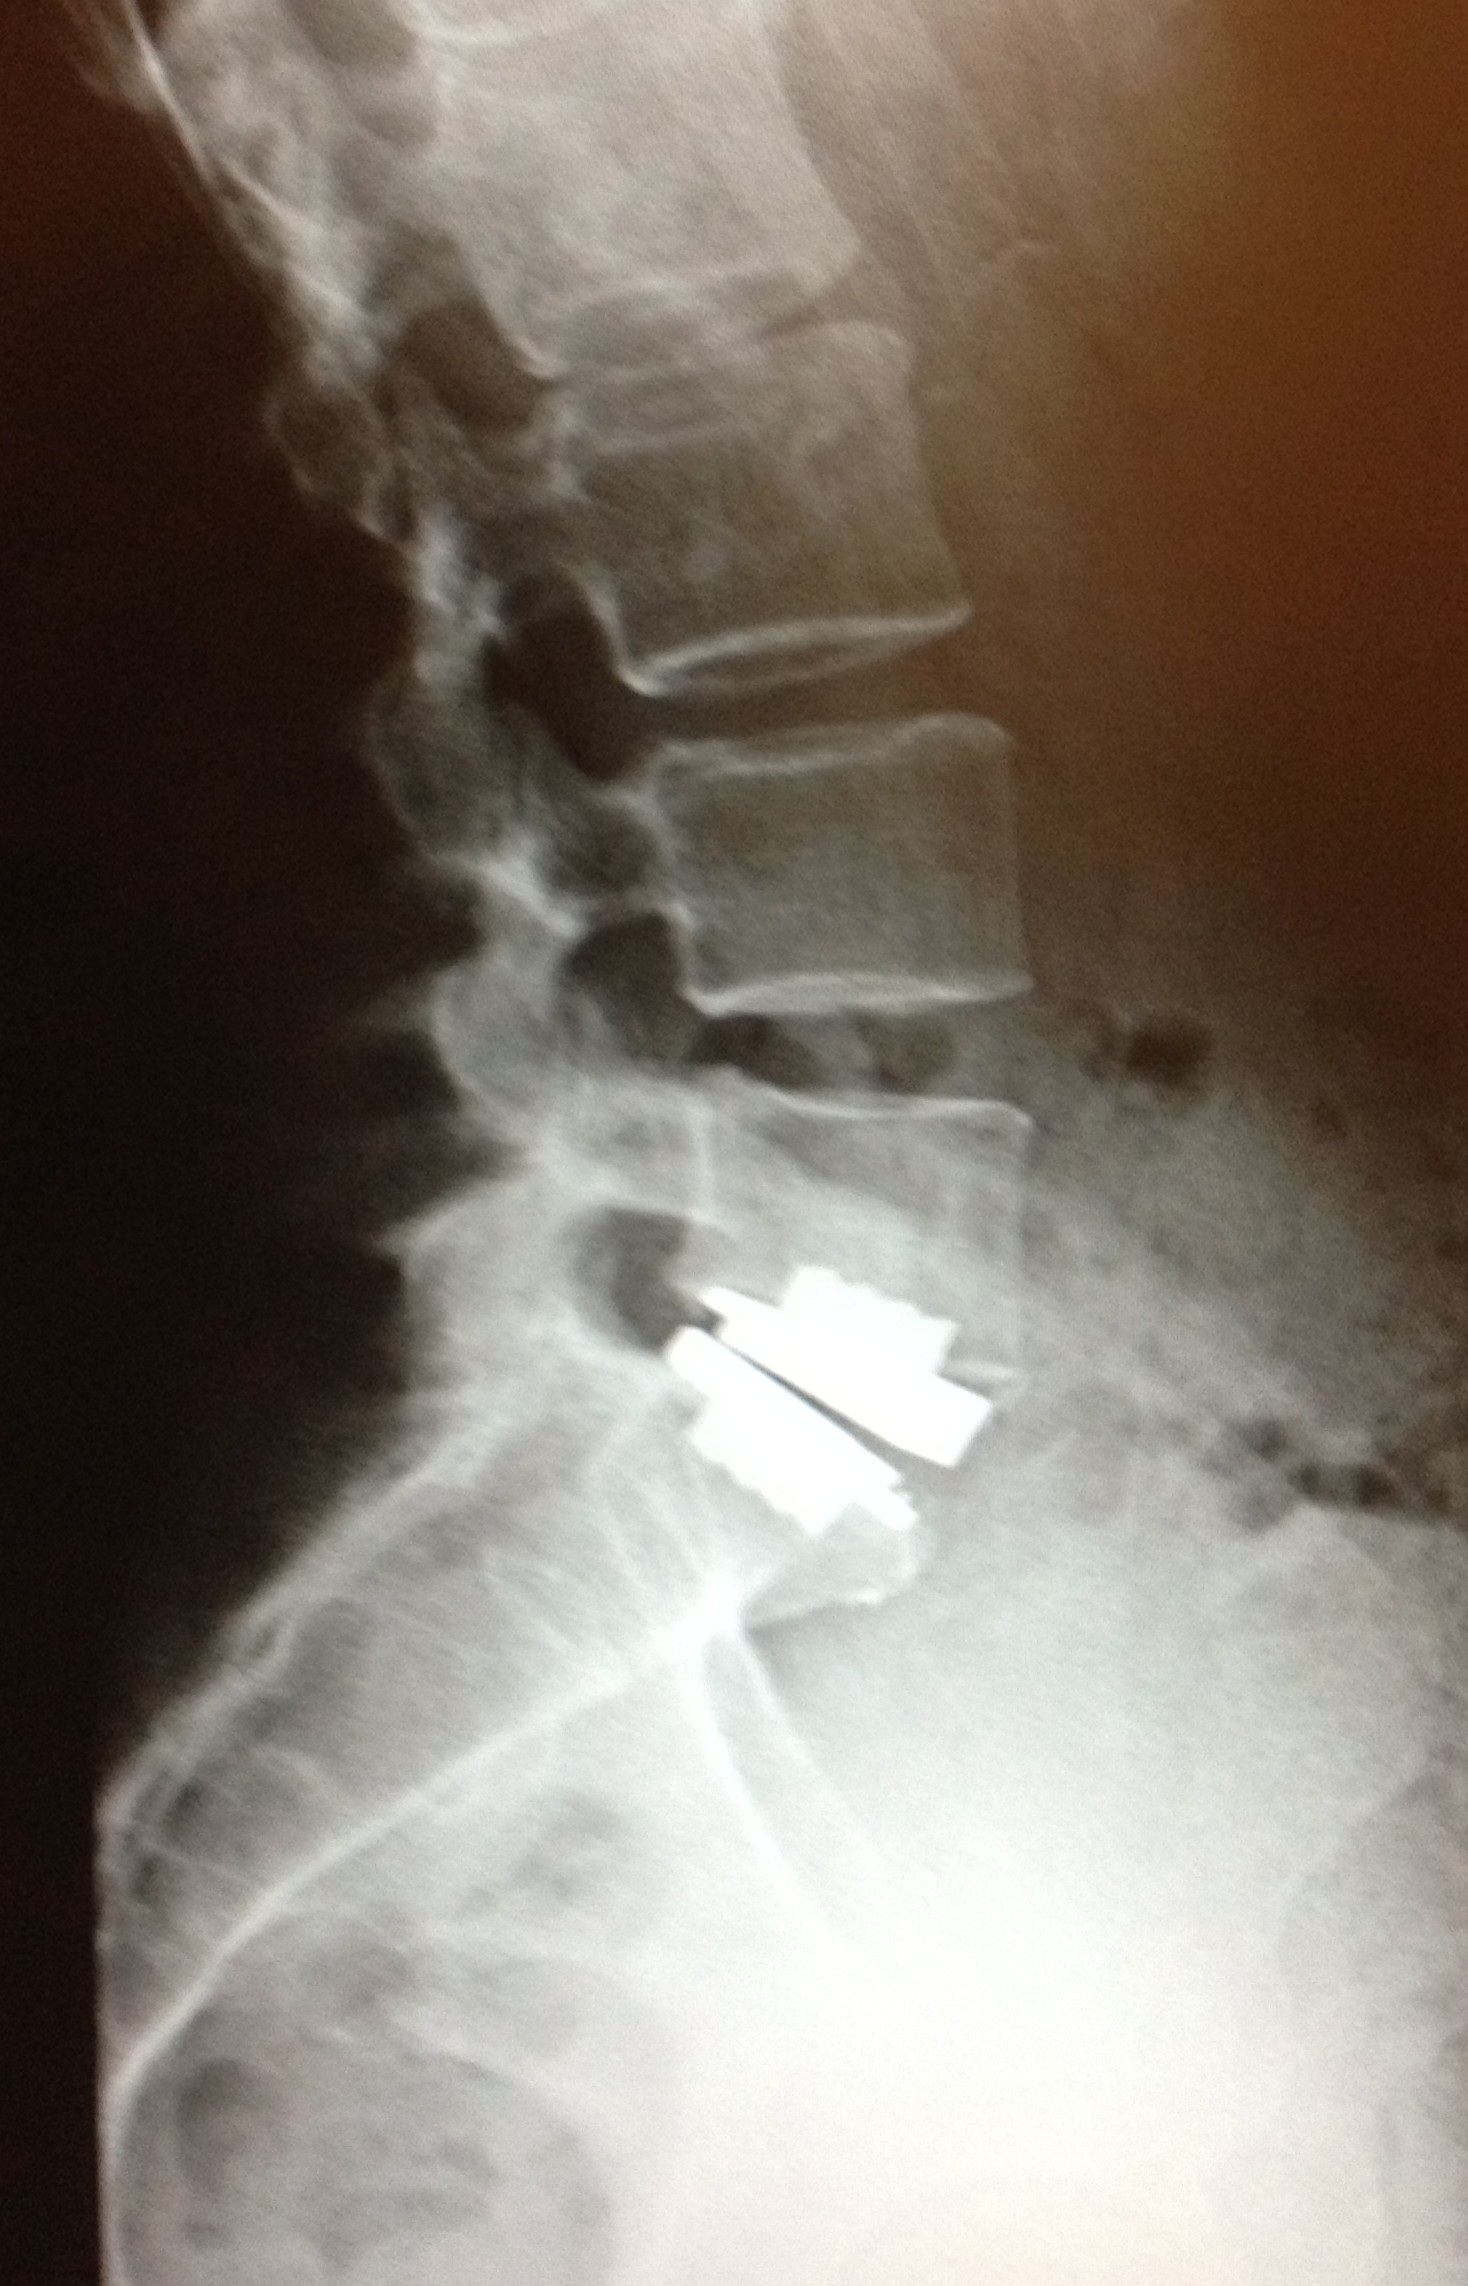

Lumbar total disc replacement is a surgical procedure in which a spinal disc in the lumbar, or lower region of the spine, is removed and replaced with an artificial disc. Also referred to as total disc arthroplasty, this spinal surgery may be indicated chronic and severe low back pain due to a degenerative or disrupted disc (degenerative disc disease).. Performed using an incision in the lower part of the abdomen, the orthopedic surgeon removes the damaged disc and associated tissue and spreads the vertebrae on either side of the disc back to their normal distance apart. The artificial disc is then inserted between the bones. At The New Jersey Spine Specialists, the procedure typically takes 1 hour and most patients go home the next day.